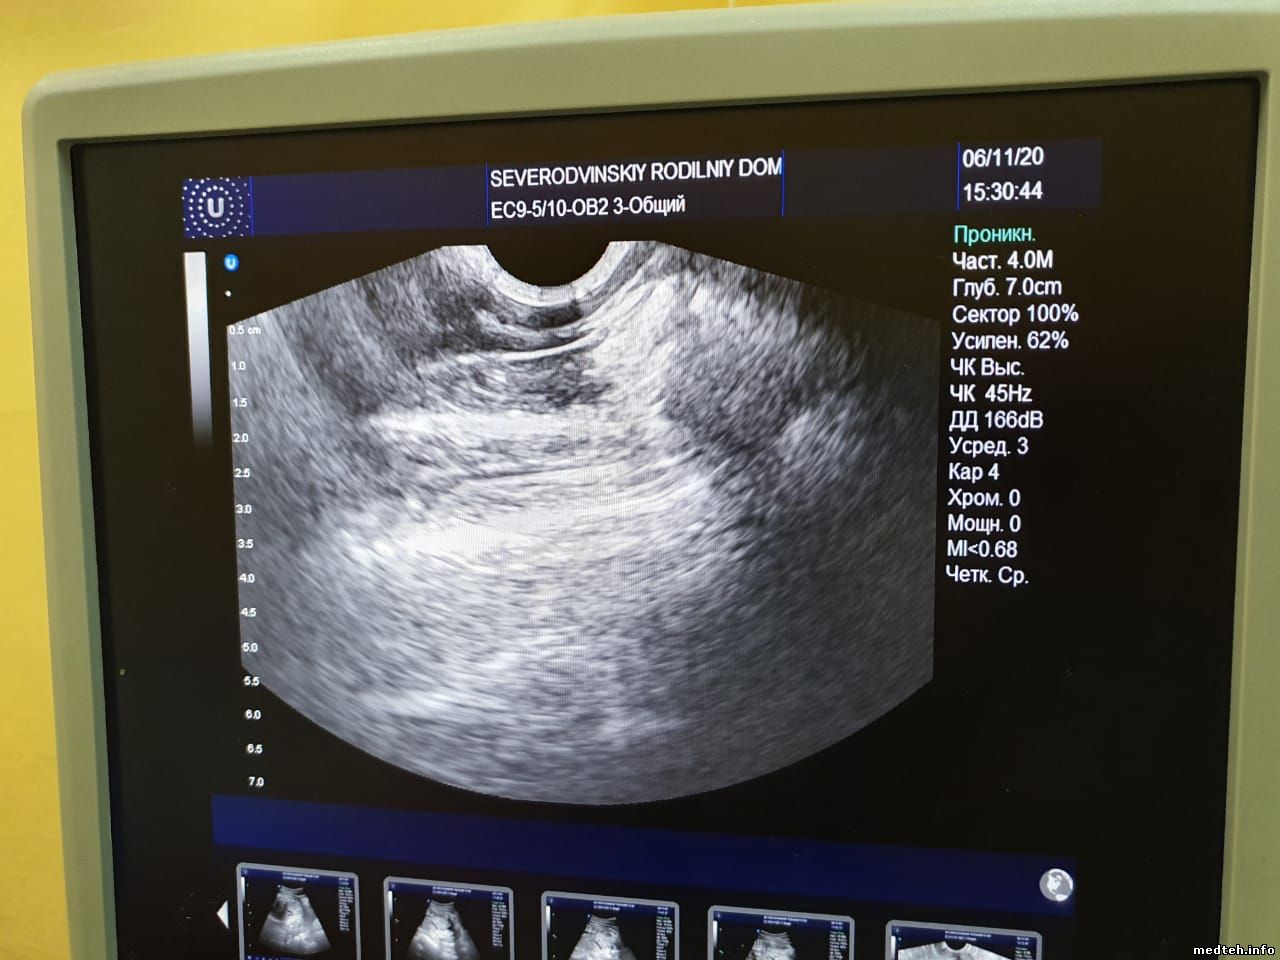

Подскажите, пожалуйста, в чем может быть проблема с датчиком?

На изображении сверху заметен сектор темнее остальных, создающий своего рода "тень", врачам мешает. При движении металлического предмета по поверхности линзы сектор в этом месте не исчезает, но тускнеет(менее яркий,чем в других частях сектора). Датчик вагинальный. С краю имеется небольшое повреждение линзы. В этом месте дефекта на изображении нет.

5377470.jpg (120.8 Kb) · 4425392.jpg (114.1 Kb) · 4316324.jpg (72.2 Kb) · 5838587.jpg (119.7 Kb)

Не уходит. В данном случае, наверное, было необязательно водить каким-то предметом. А вообще, чтобы проверить ПК. Если "выбиты", то в этом месте на секторе будет "провал". Разве нет? ...

9643944.jpg (24.5 Kb) · 9487175.jpg (89.1 Kb)

Похоже, что у вас есть повреждение ПК, но возможно, что может проблема в разъёме.

Если пару ПК у вас неисправны, то как раз примерно такое поле будет невидным.

Сектор выпадает, когда есть повреждение нескольких рядом (по моему опыту).

С такой дыркой в линзе Вы планомерно убиваете датчик, и судя по теням у Вас это получается неплохо.

Мы однозначно можем помочь решить Ваши проблемы. остальное написал Вам в личный ящик.